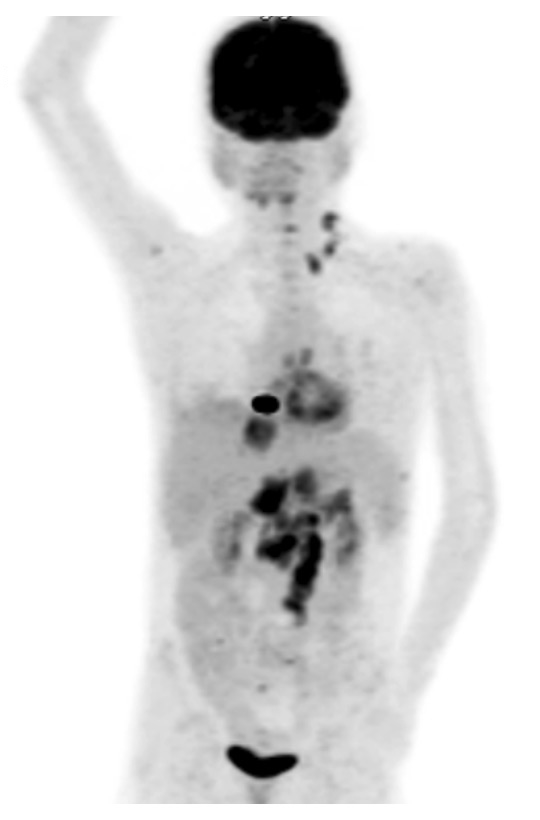

Figure 1

Positron emission tomography-computed tomography scan showing fluorodeoxyglucose uptake in the liver, bones and lymph nodes (highlighted Virchow’s node in the left supraclavicular area).

In August 2013, an abdominal ultrasound was performed because of diffuse epigastric pain, which showed several hepatic lesions. The MRI revealed coeliac, retroperitoneal and hilar hepatic lymphadenopathy. PET-CT detected fluorodeoxyglucose (FDG)-enriching lesions in the bones and in the supraclavicular lymph nodes (“Virchow’s node”, fig. 1). Fine needle aspiration of the latter showed adenocarcinoma cells, probably of gastrointestinal origin. Endoscopy confirmed the presence of a gastric tumour, which was found to be a poorly differentiated adenocarcinoma on biopsy. Probably as a result of paraneoplastic thrombophilia, the patient developed multiple venous thromboses and a fatal event of pulmonary embolism with fulminant right heart failure led to death. In the previous 12 months, the median trough (C0) CSA level was 44 μmg/l (target level calculated from the area under the concentration-time curve [AUC]: 50–70 μg/l), the MMF dose 1000 mg BID and the PDN dose 5 mg ID (maintenance dose 0.1 mg/kg/day, body weight 35 kg).